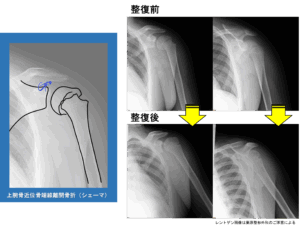

子どもの交通事故では骨折や脱臼が隠れていることも

交通事故では、打撲や捻挫のように見えて、実は骨折を伴っているケースもあります。

特に成長期の子どもは、骨に骨端線(成長軟骨)があるため、大人とは異なる形の骨折が起こることがあります。

事故直後は動かせていても、数日から数週間経ってから腫れや痛み、動かしにくさが強くなることがあり、初期には見逃されやすい点に注意が必要です。

また成長期の子どもでは、骨や関節がまだ発達途中にあるため、小児骨折の場合、その時点では問題がなくても、成長の過程で成長障害として現れることがあります。

そのため、痛みの強さだけで判断せず、回復の経過を慎重に見ていくことが大切です。